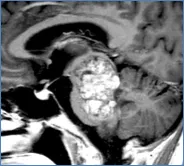

当孩子确诊脑干海绵状血管瘤那天,我感觉天都塌了。 直到现在,我还能清晰想起2020年那个初秋的下午,医生把CT片递到我手里时的场景窗外的阳光明明很暖,我却觉得浑身发冷,手里的片子...